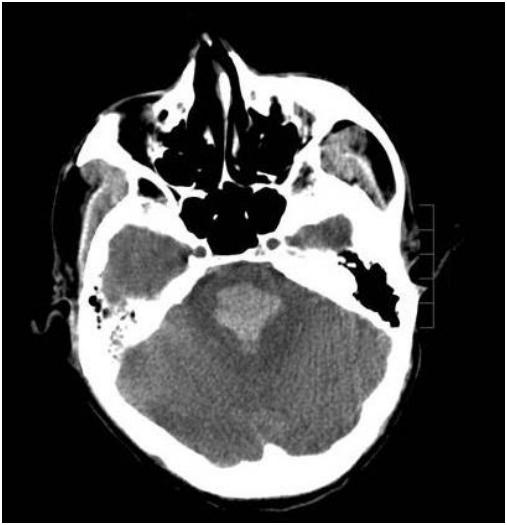

37岁的脑干出血

过年的时候收了一位37岁,家属不清晰患者有没有高血压,但近两年经常头疼,大年三十喝了不少酒,晚上玩了一夜麻将,初一上午9点多突然叫不醒昏迷被送到医院!

查头CT见是脑干出血,患者出现呼吸间停,收到我们科后给予气管插管,呼吸机辅助呼吸,气管切开了!

4、脑干并不是一个部位,它包括中脑,脑桥,延髓三部分,不同部位出血症状是不一样的,但这些地方都很重要,一般如果出血5毫升以上就算出血量大的,预后相对较差。